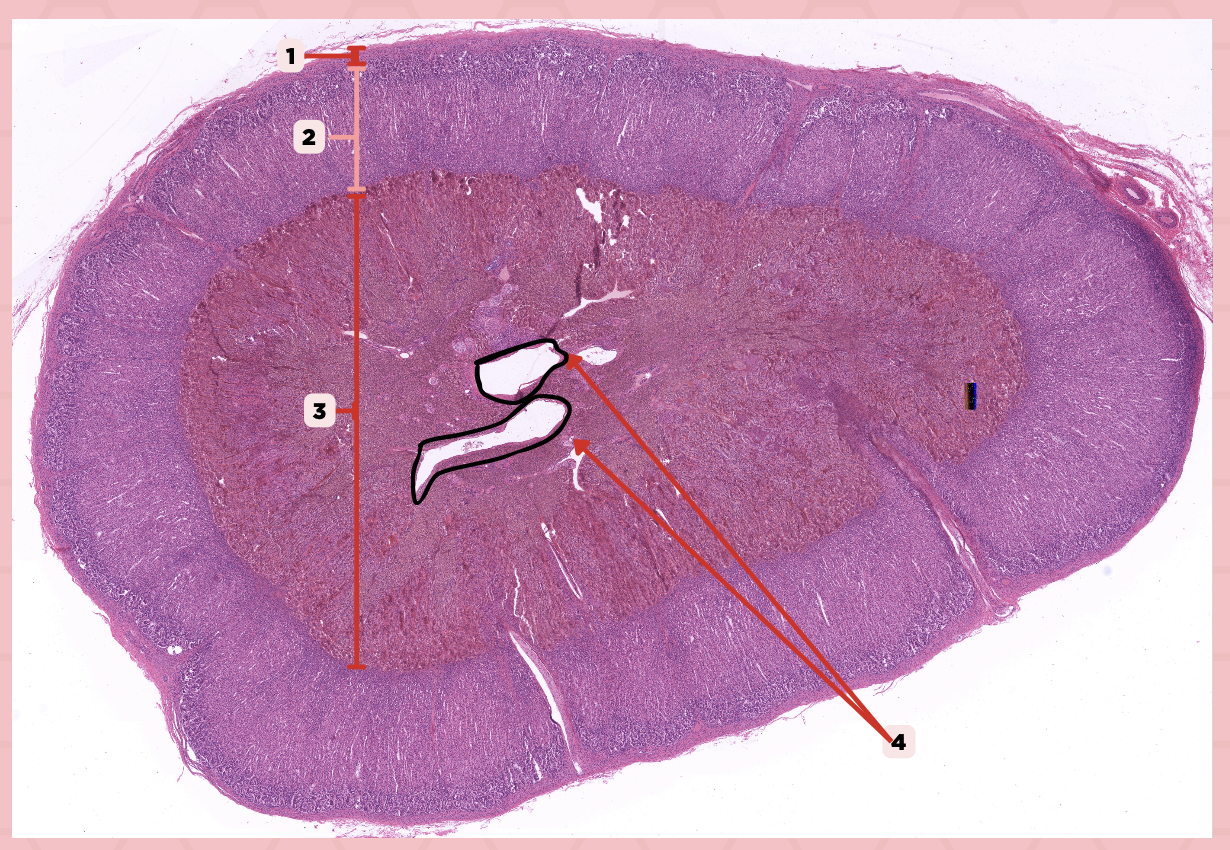

Identify the specimen.

Anterior Lobe

Identify the structure labeled as 1.

Posterior Lobe

Identify the structure labeled as 2.

Intermediate Lobe

Identify the structure labeled as 3.

Pars Tuberalis

Identify the structure labeled as 4.

Pituitary Stalk

Identify the structure labeled as 5.